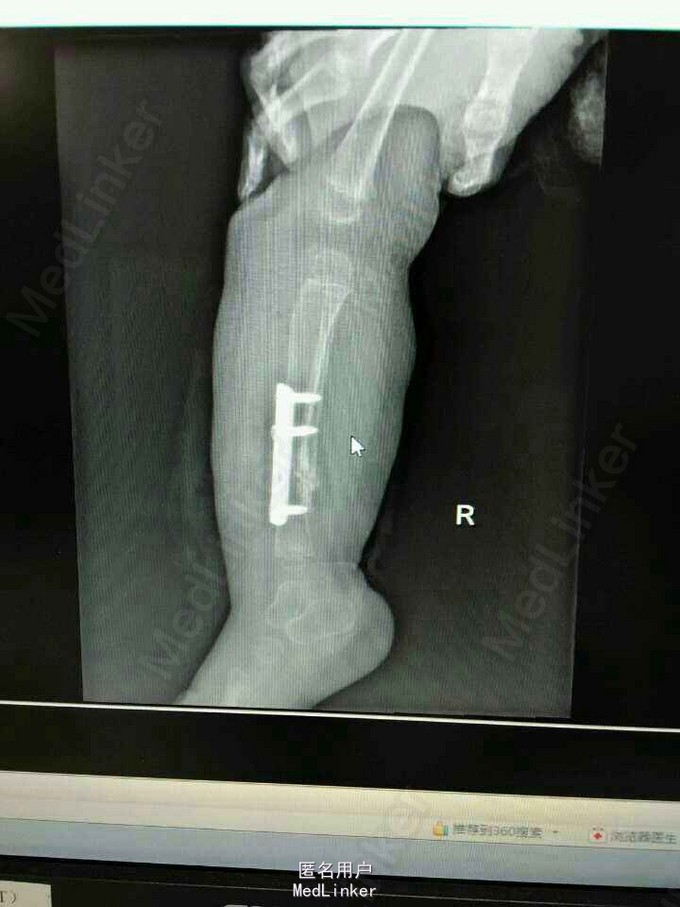

患女1岁8个月,患者母亲诉小孩出生时右小腿畸形,1岁时学走路跌倒后哭闹数天,小腿肿胀去医院检查示右胫腓骨折,稍做固定,1岁3个月时复查骨折未愈合,考虑先天性胫骨假关节,行手术治疗,现术后5个月复查未愈。目前小儿不能行走。

神经纤维瘤病,先天性胫骨假关节。该患者经过讨论及与家属多次沟通愈后情况,行病灶切除,取母体骨移植,AO锁定钢板内固定,暂时管型石膏外固定,并订制支具